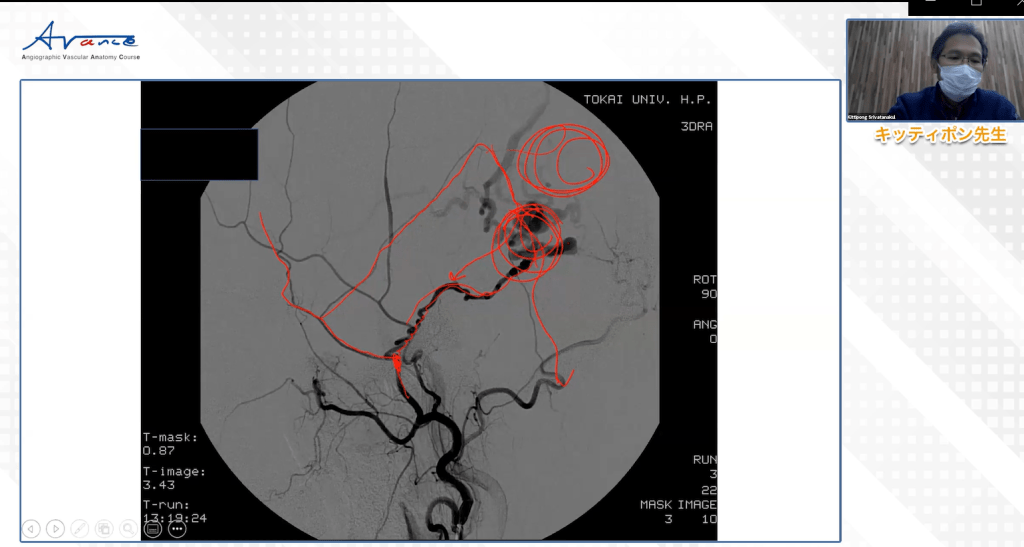

テーマ: 初心者のための硬膜動静脈瘻の理解と読影に必要な血管解剖

当日の風景というものはほぼ画面上のものですが、以下に共有させていただきます。